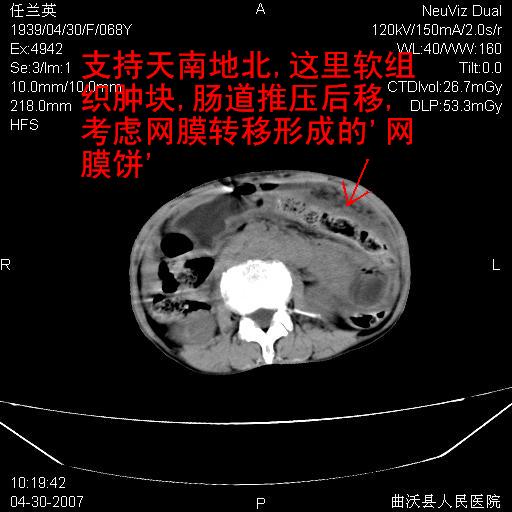

难的一见 典型 - 网膜饼  冰冻骨盆 可以当教学片了

支持左侧卵巢恶性肿瘤伴网膜、腹膜广泛转移。

支持:左侧卵巢恶性肿瘤伴网膜、腹膜 腹膜后(淋巴结)广泛转移。

网膜、腹膜广泛转移考虑来源于左侧卵巢癌可能性大。不除外来源于消化系的肿瘤。